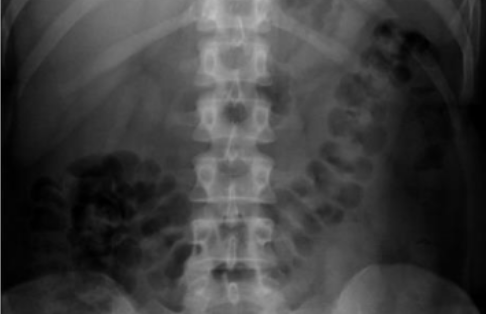

What is this and what type of scan

Large bowel, AXR